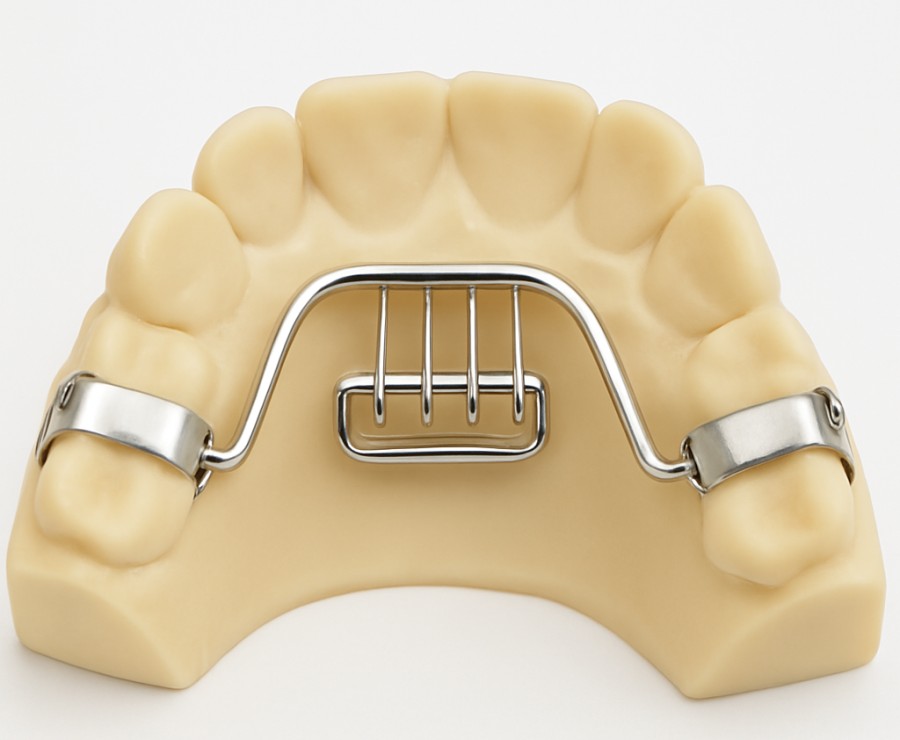

Jaw growth problems, bite issues, and misaligned teeth in children and adolescents can often be corrected with the right appliances at the right age. At Elite Dental Care and Aesthetics, our functional and orthopaedic appliances guide proper jaw development, correct bite irregularities, and support healthy, long-term dental alignment.

What do functional & orthopaedic appliances include?

Growth Guidance – Appliances that influence jaw growth in children, ensuring proper alignment of upper and lower jaws.

Bite Correction – Helps correct overbites, underbites, and crossbites at an early stage.

Muscle Training – Encourages proper tongue, lip, and jaw function for balanced facial development.

Orthopaedic Appliances – Special devices that gently modify bone growth to achieve harmony between teeth and jaws.

Combined Therapy – Can be used before, during, or after braces for lasting results.

Why choose functional & orthopaedic appliances?

Corrects Jaw Growth Early – Prevents severe misalignment in adulthood.

Improves Oral Function – Enhances chewing, speech, and breathing.

Supports Aesthetics – Promotes a well-balanced facial profile.

Reduces Need for Surgery – Early intervention avoids complex future treatments.

Long-Term Benefits – Creates a strong foundation for healthy, aligned teeth.

At Elite Dental Care, we customize each appliance to your child’s needs, ensuring comfort and effective results. Our goal is to guide proper growth, correct functional habits, and provide a healthy smile that lasts a lifetime.